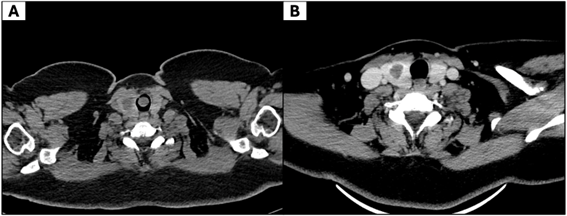

Since 2018, her asthma symptoms had progressively worsened despite adherence to treatment. At that time, pulmonary function tests revealed no significant abnormalities. Due to persistent symptoms, computed tomography (CT) of the neck and chest was performed, which revealed a pedunculated, hypodense mass measuring 14 × 13 × 3 mm, arising from the anterior tracheal wall at the first tracheal ring, causing significant luminal obstruction (Figure 1A), while post-excision CT showed no residual disease (Figure 1B).

Figure 1. Computed tomography (CT) of the trachea. (A) Axial CT demonstrates a pedunculated, solid mass in the proximal trachea, arising from the anterior wall and partially obstructing the airway lumen. (B) Post-excision CT shows no residual disease, with no pathological wall thickening or abnormal enhancement.

Following bronchoscopic intervention, the patient’s respiratory symptoms resolved completely. At six-month follow-up, CT imaging (Figure 1B) and bronchoscopy were performed. The bronchoscopy revealed a mucosal protrusion, as shown in Figure 2C, which was biopsied and showed respiratory epithelium without evidence of residual neoplasm. Clinically, the patient was symptom-free, with unrestricted daily activities and no radiological or endoscopic signs of recurrence.